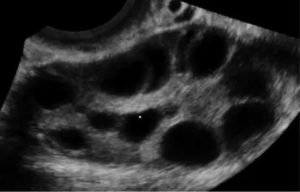

Важно! В большинстве случаев мультифолликулярные яичники у пациенток обнаруживается случайно при прохождении УЗИ. Обычно такие железы имеют обычные размеры, их капсула не изменена. Количество пузырьков не превышает 10, диаметр их колеблется от 4 до 8 мм.

Эхопризнаки мультифолликулярных яичников

Врач ультразвуковой диагностики при проведении ультразвукового обследования без труда определяет МФЯ. Их основные эхографические признаки мультифолликулярных яичников:

- Размер яичников незначительно превышает норму;

- Эхогенность (способность ткани по-своему отражать ультразвуки) у яичников меньше, чем у матки;

- Множественные (более 20) антральные фолликулы (структуры с высокой вероятностью дозревания), их размер не превышает 9 мм;

- Доминантный фолликул не имеет утолщенной капсулы;

- Расположение антральных фолликулов диффузное (разбросанное).